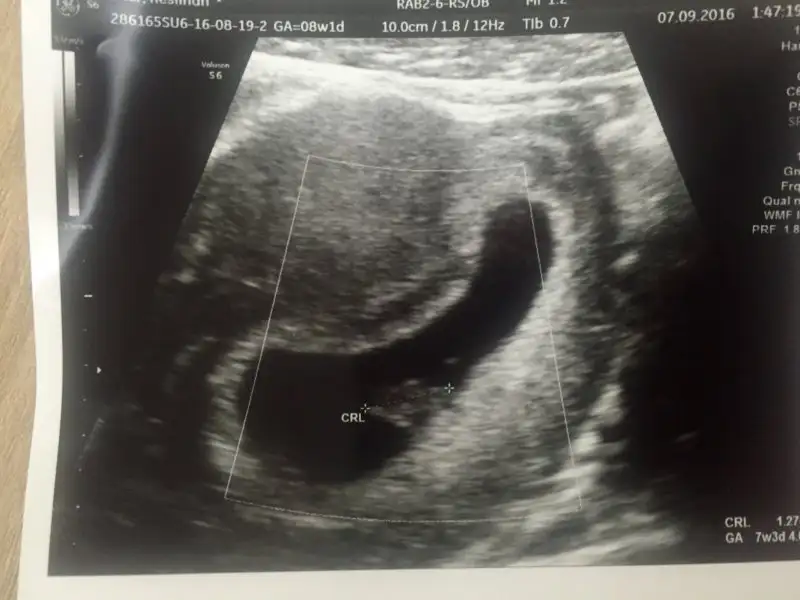

Cnm eger karindan ise bu goruntu seninki biraz ortada gibi ama sola daha yakın kız gibi görünüyor. Allah sağlık versin inşallah hepsine.Canlarım bu da benim bebiş. Daha bu aşamada bile tahmin edenler varmış cinsiyetini. Bilen var mı? Sizce ne?

Eğer karından usg ise erkek gibi :)Canlarım bu da benim bebiş. Daha bu aşamada bile tahmin edenler varmış cinsiyetini. Bilen var mı? Sizce ne?